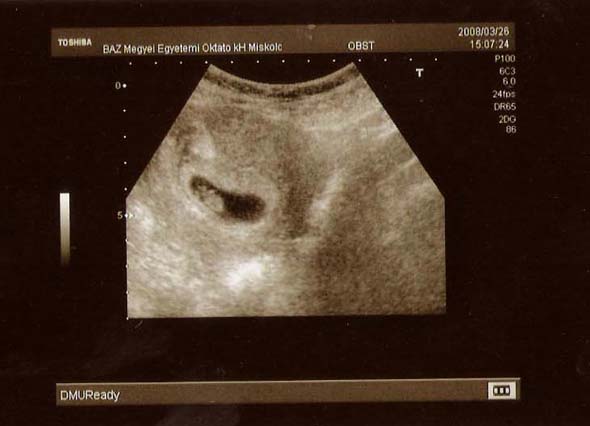

Íme Kistöki első képe:

Kép